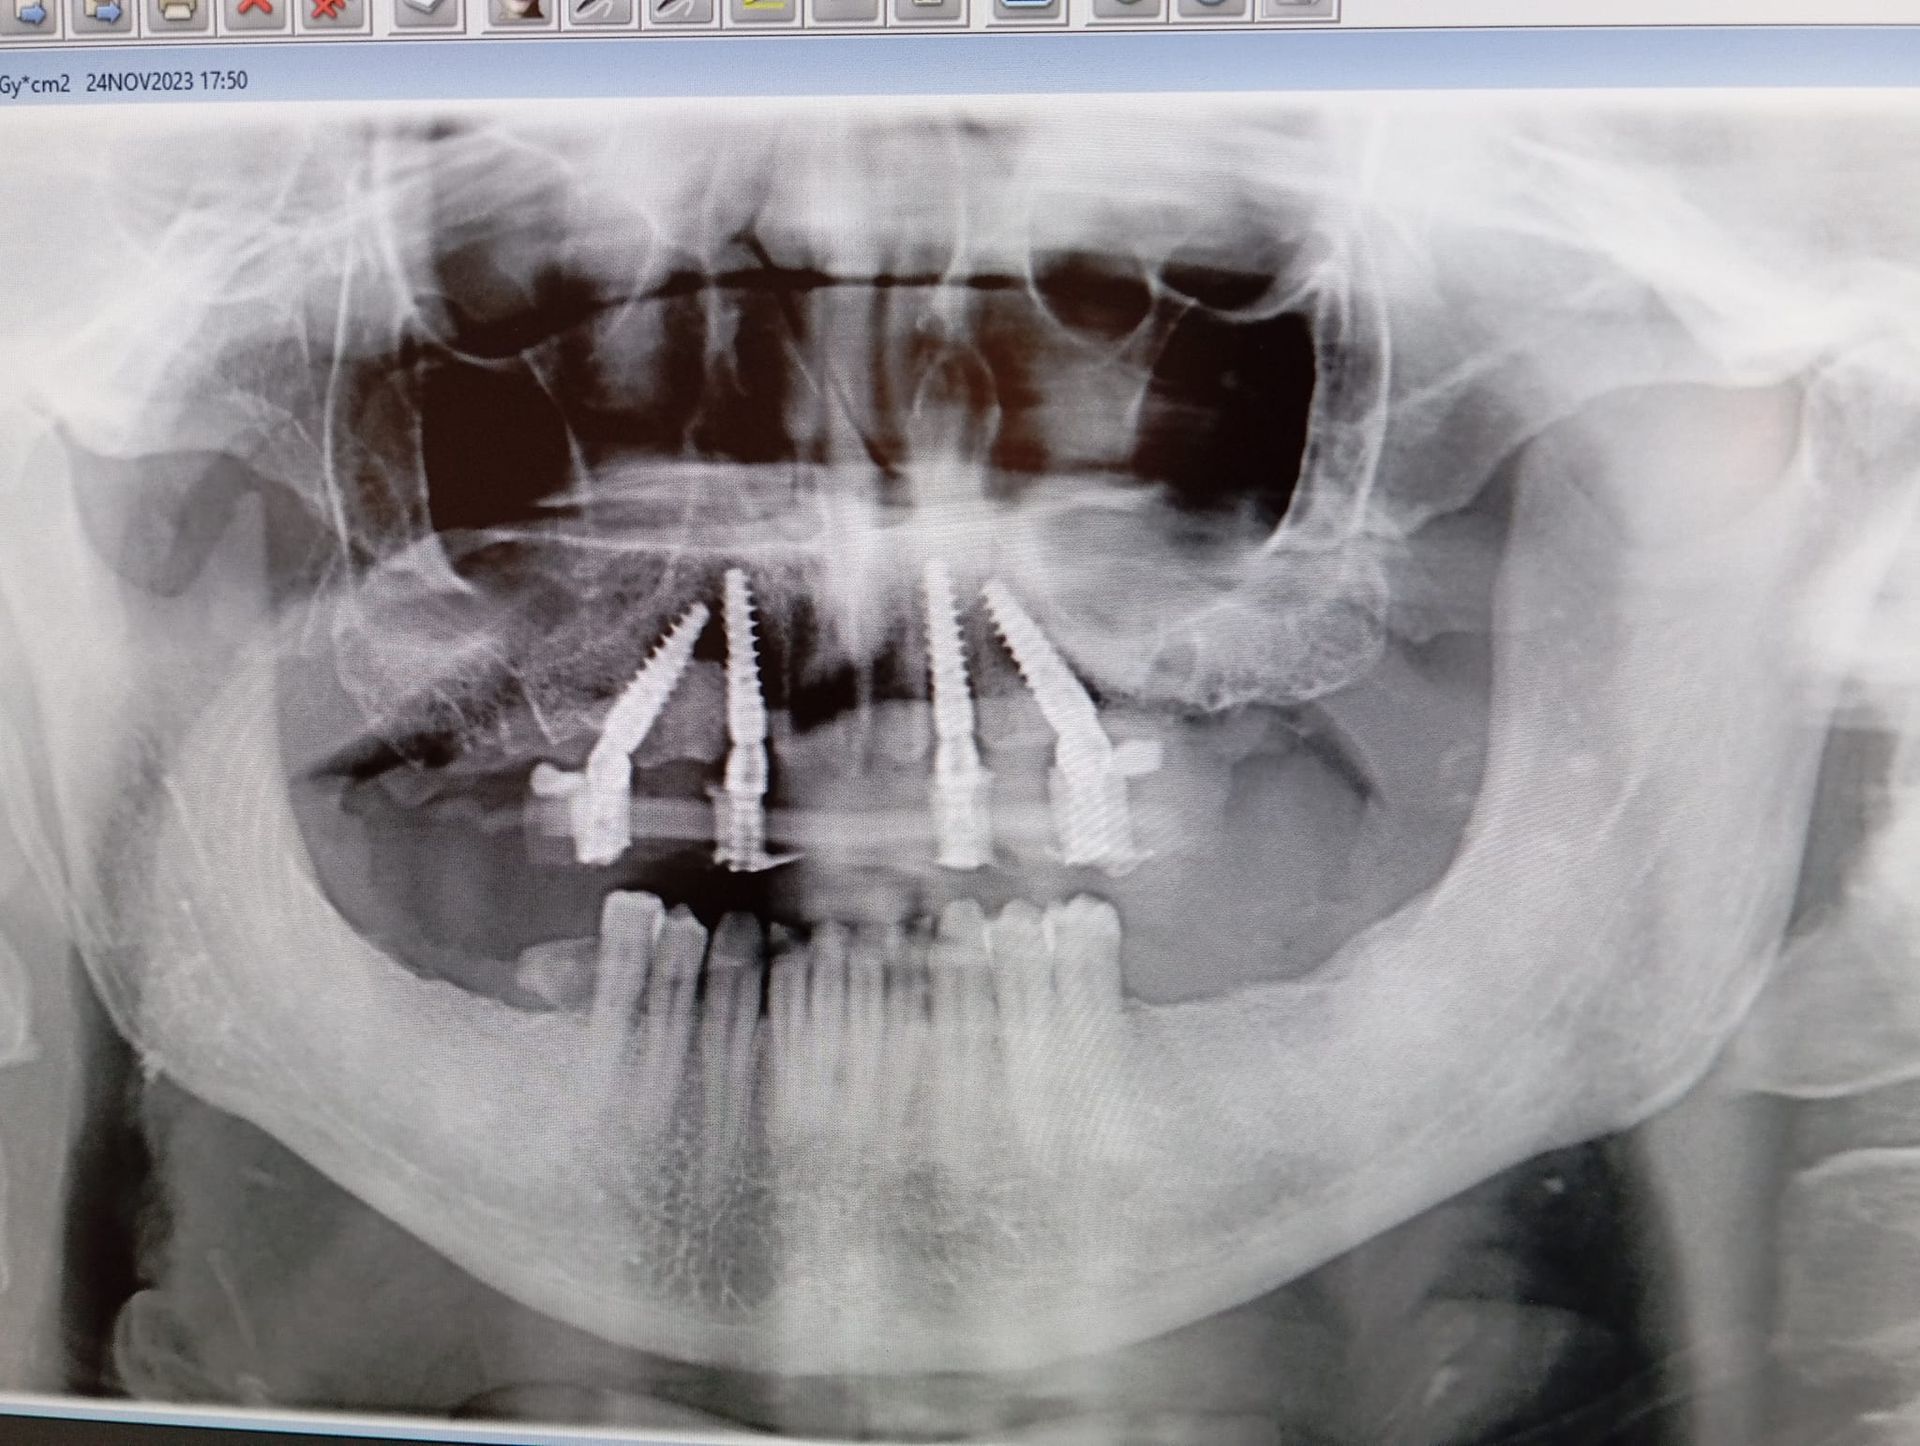

L’implantologia dentale è una branca dell’odontoiatria che ha l’obiettivo di ripristinare i denti mancanti mediante l’inserimento di radici artificiali in titanio (impianti dentali).

Le tecniche di implantologia dentaria permettono una riabilitazione permanente della masticazione

ed evitano i fastidi legati all’utilizzo di protesi mobili, assicurando un risultato estetico

pari a quello dei denti naturali.